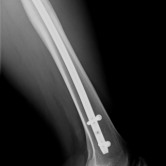

Röntgenbilder